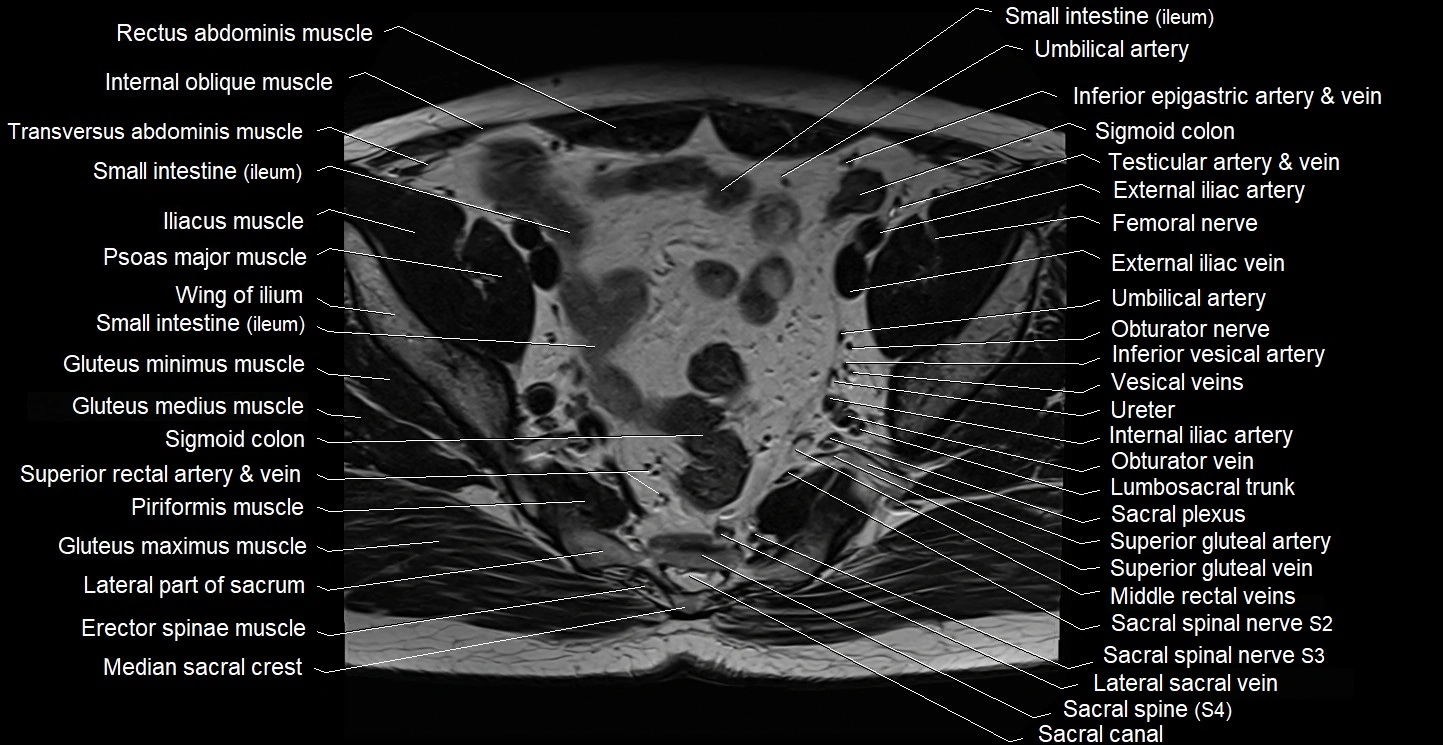

- External iliac artery

- External iliac vein

- Gluteus maximus muscle

- Gluteus medius muscle

- Gluteus minimus muscle

- Internal iliac artery

- Internal iliac vein

- Lateral sacral vein

- Lumbosacral trunk

- Median sacral crest

- Piriformis muscle

- Psoas major muscle

- Sacral canal

- Sacral plexus

- Sigmoid colon

- Superior gluteal artery

- Superior gluteal veins

- Transversus abdominis muscle

- Umbilical artery

- Vesical veins